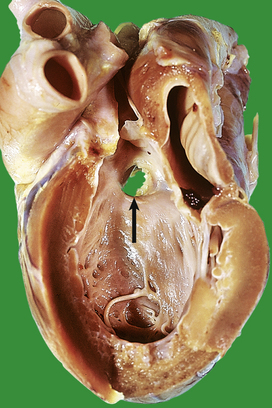

Mycotic aneurysms are the result of weakening of the arterial wall, secondary to bacterial or fungal infection. The organisms are thought to reach the arterial wall via the blood stream and enter the media via the vasa vasorum. Lesions are commonest in the cerebral arteries (Fig. 13.10) but almost any area can be affected. Bacterial endocarditis is the commonest underlying infection.

image

Fig. 13.10 Mycotic aneurysm in brain. This patient had infective endocarditis. A mycotic aneurysm (arrow) has ruptured. There is haemorrhage into the basal ganglia, which has extended into the subarachnoid space.